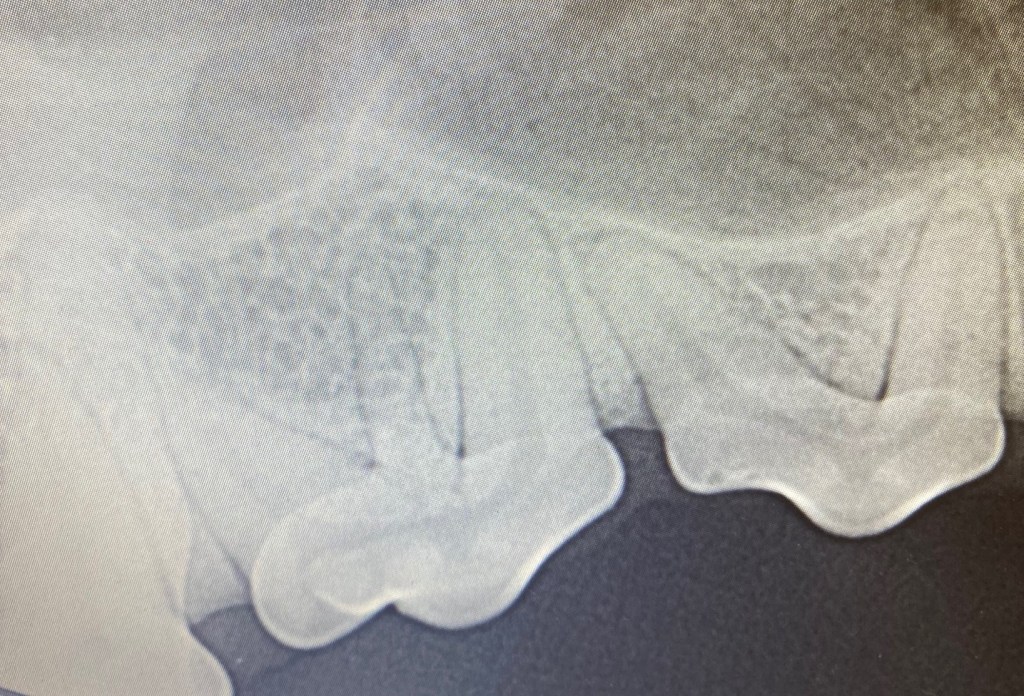

Two upper left canine teeth in a 13 year old cat. The vet who sent this image to me said both the canines were solid. Interestingly it had not ever been mentioned to the owner by the previous vet! Remember….always look in the mouth if possible and safe during EVERY consultation…who knows what you will discover! If this cat were to have a dental X-ray, it would likely show that the distal canine is in fact a retained deciduous tooth.